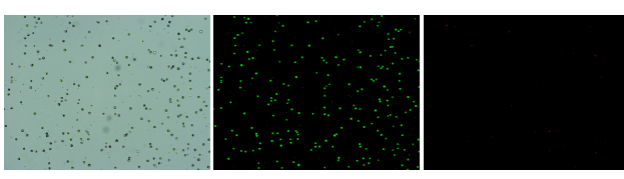

肝臟是人體代謝和解讀的器官,在體內(nèi)發(fā)揮氧化、儲(chǔ)存肝糖、合成分泌性蛋白合成等,肝臟也制造消化系統(tǒng)中之膽汁,人肝約有25億個(gè)肝細(xì)胞。但是解離肝臟組織懸液并不簡單,首先,肝臟代謝旺盛,離體后肝細(xì)胞無法進(jìn)行正常的有氧糖酵解,細(xì)胞活力會(huì)迅速下降,另外,肝細(xì)胞的線粒體很多,每個(gè)細(xì)胞大約有1000個(gè)左右,遍布于胞質(zhì)內(nèi)。因此,很難得到符合單細(xì)胞測(cè)序要求的單細(xì)胞懸液。百邁客生物在肝臟組織單細(xì)胞懸液制備方面有豐度的實(shí)操經(jīng)驗(yàn),開發(fā)了獨(dú)有的解離體系,下面來看實(shí)驗(yàn)結(jié)果:

實(shí)驗(yàn)結(jié)果

人肝癌樣本,懸液背景干凈,活性91.69%,結(jié)團(tuán)率6%